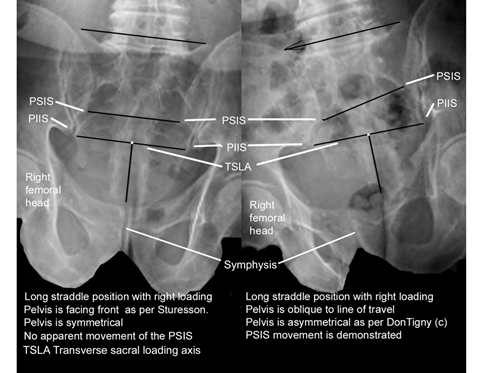

Sturesson in 198910 used tiny tantalum balls implanted in the pelvis, measured pelvic movement in the long straddle position (LSP) and reported finding about 2 degrees of movement at the SIJ. Smidt in 1995,11 using a different method for the measurement of movement of the SIJ in the LSP, reported finding about 30 degrees of motion.

There were no obvious errors in measurement, but Sturesson had blocked the pelvis in the frontal plane in the LSP for his measurements.10 In the LSP the pelvis is asymmetric and oblique to the line of travel to extend the length of the stride. When Sturesson blocked the pelvis he inadvertently blocked it in a position of symmetry and simply measured the symmetrical pelvis in the LSP with the right leg advanced and again with the left leg advanced.10 All he measured was a minimal movement in the symmetrical pelvis. This was a fatal error in procedure.

I had myself x-rayed in the LSP with the pelvis in asymmetry with counter rotation right and left (Figures 2&3).8,9 The x-rays clearly showed the posterior rotation of the innominate bone on the side of loading moving the sacrum caudad, but not moving caudad on the sacrum. The innominate on the contralateral side lifts the sacrum on that side to cause lateral sacral flexion with rotation toward the side of loading.

I also did one view in the LSP with the pelvis blocked in the frontal plane, as per Sturesson and the symmetrical pelvis in that position is obvious (Figures 4 & 5).7–9

In the x-ray on the left the lack of movement at the PSIS demonstrates that the pelvis is symmetrical even though the subject is in the long straddle position. Note in the right x-ray that with posterior rotation on the loaded side the innominate causes the sacrum to move caudad, but does not move caudad on the sacrum.